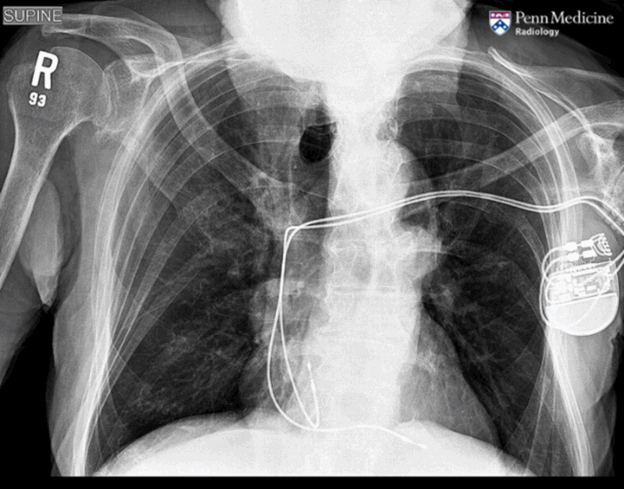

90-year-old man with left neck mass and loss of appetite

A 90-year-old man presented to the emergency department with two months of enlarging left neck mass and loss of appetite.